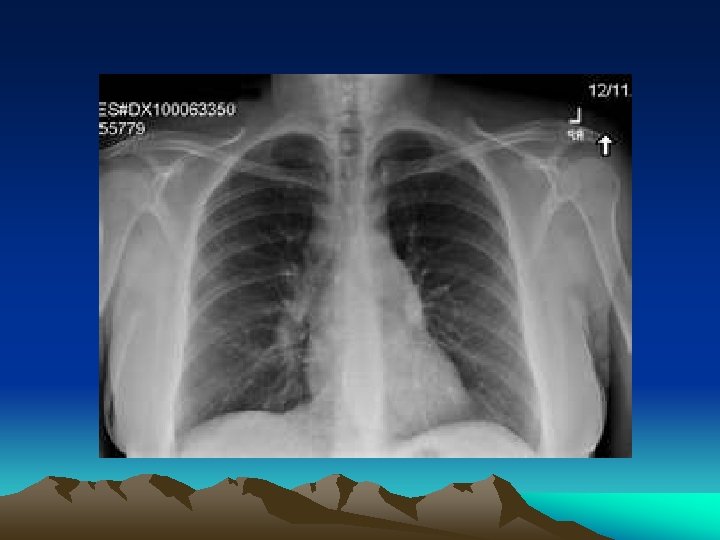

Zánět pohrudnice Pneumothorax Zápal plic